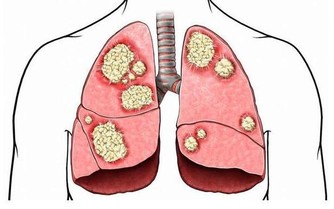

雖然發作性睡病發作時症狀比較明顯,但是有時因為各種原因,也會常出現嗜睡的情況,比如夜間睡眠不足、抑鬱症、藥物不良反應、慢性阻塞性肺病、甲狀腺功能減退等。